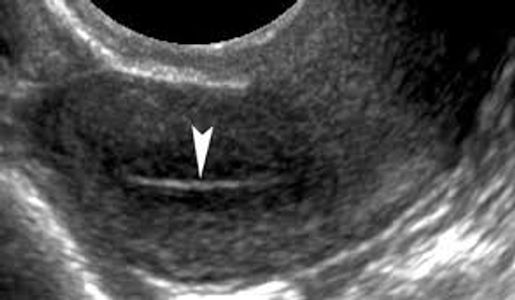

Endometrial polyps show as focal echogenic areas which obscure the normal central interface. A vascular pedicle, when present, helps to confirm a polyp.

Endometrial atrophy is the most common cause of bleeding among postmenopausal women. This may also occur from hormonal suppression- such as oral contraceptives.

Hyperplasia may be seen with excessive unopposed estrogen, tamoxifen and in some patients with polycystic ovarian syndrome. Endometrial hyperplasia is usually caused by an excess of estrogen without progesterone (female hormones). The lining of the uterus is not shed if ovulation does not occur. This means that the endometrium may continue to grow in response to the production of estrogen. The cells of the endometrium may abnormally crowd (hyperplasia), which may lead to the cancer of the uterus.